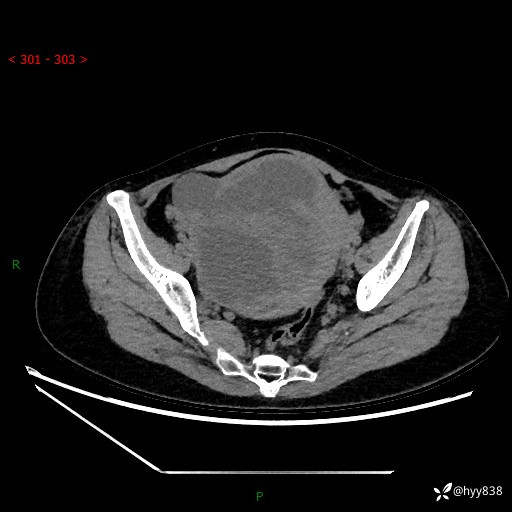

辅助检查:CT

增强(动脉期+静脉期)